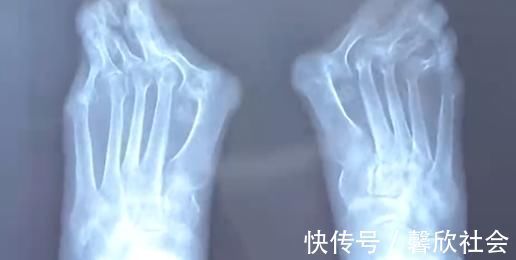

由于高跟鞋的挤压,王女士的左脚大脚趾变成了两个脚趾,随着时间的推移,大脚趾一侧又多了一个 \\'\\'拐\\'\\',现在只能通过手术来缓解症状。除了鞋子不当,遗传和疾病因素也是造成拇指外翻的原因,70 岁的高女士患风湿病,脚也发生了接近 60 度的严重变形。

忍痛十几年,直到前几天,高女士连男士的鞋子都穿不上,眼看着不能走路了才来到医院就诊,而这时手术的风险和难度都增大很多。